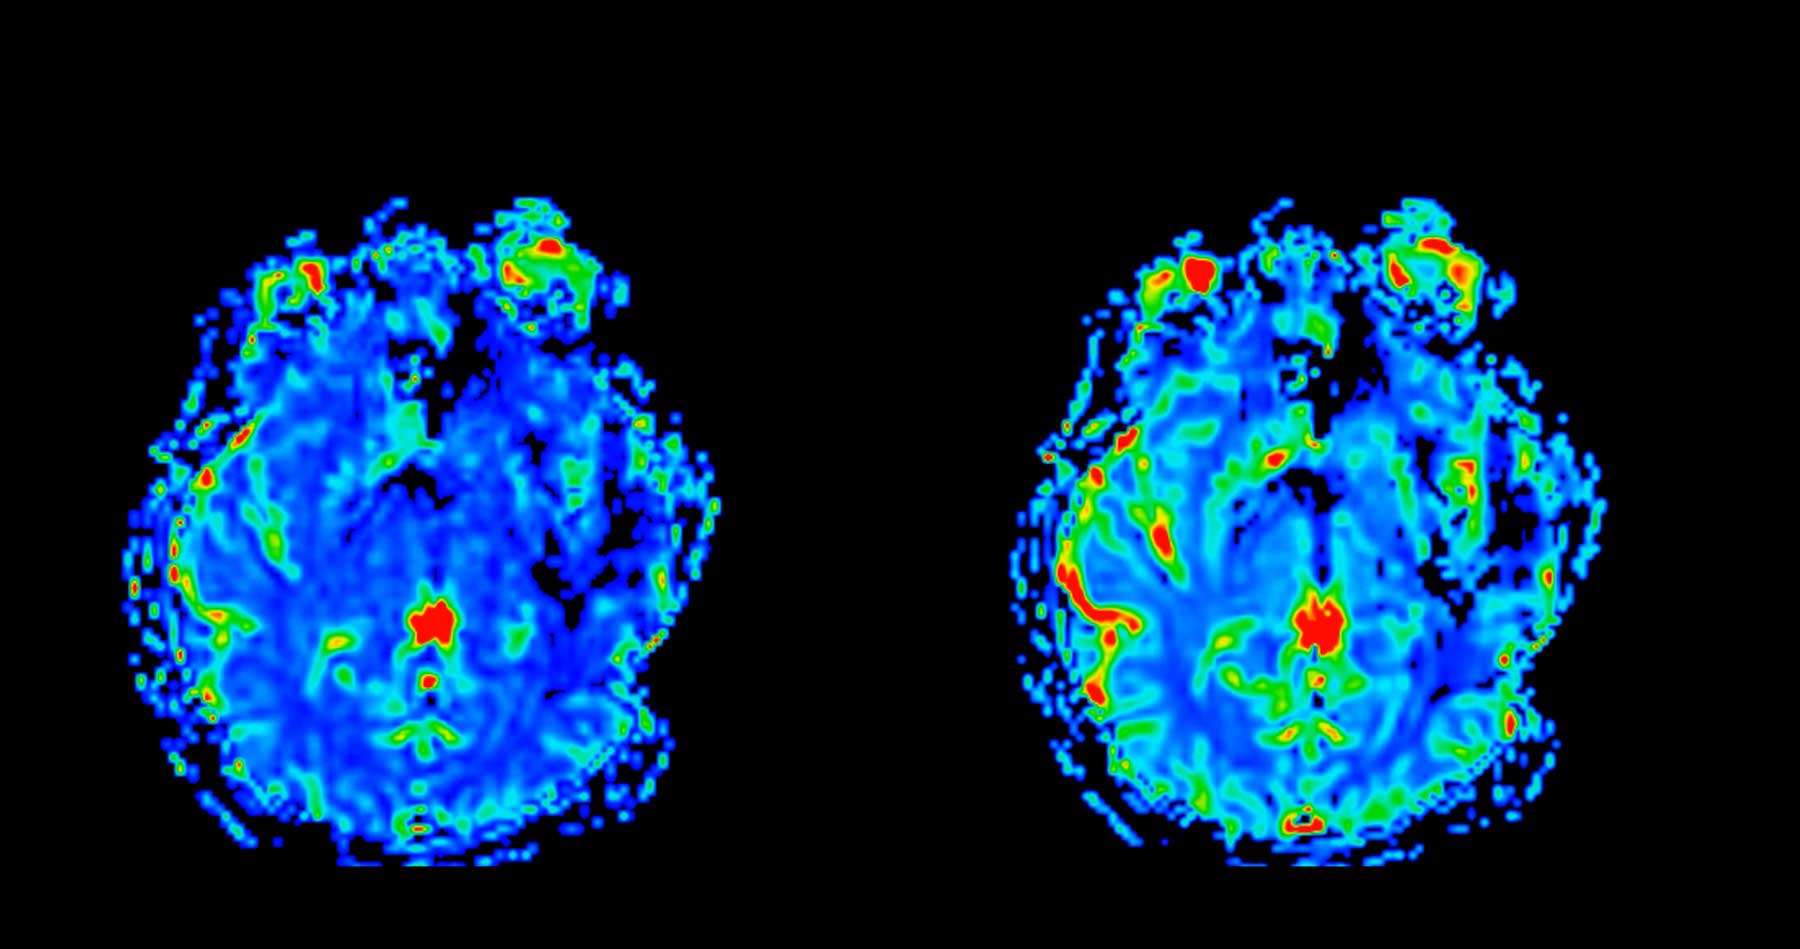

One of the dyes illuminated tau clumps in an animal model of Alzheimer’s disease, as well as samples taken from deceased Alzheimer’s patients.